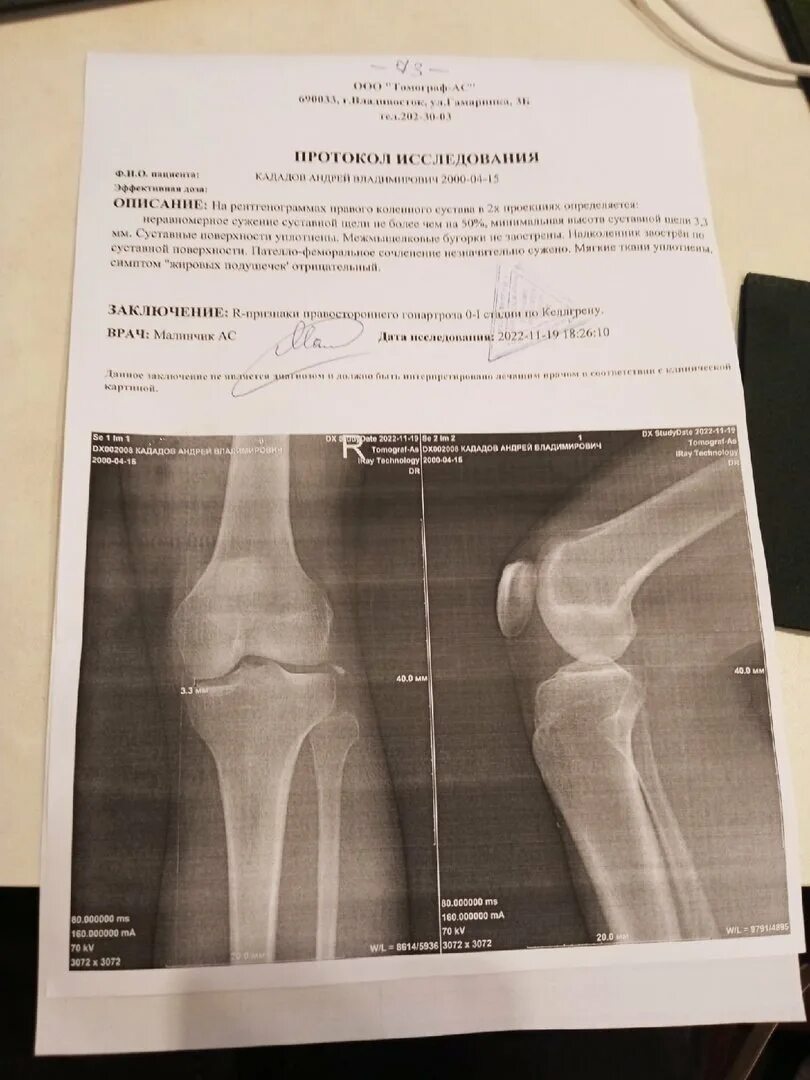

Суставная щель 3 3 мм